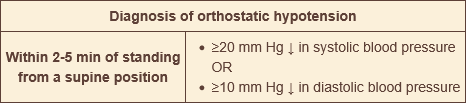

what is the cutoff for orthostatic hypotension?